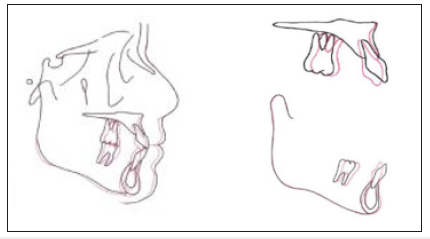

Figure 5:Cephalometric superimposition.

After extraction of bilateral lower first premolars, the initial leveling and alignment were performed, followed by loop mechanism for space closure. Intermaxillary elastics were used to achieve maxillary space closure. After closing all the space of both arches and detailing, canine recontouring was performed. The patient was satisfied with the treatment results after two years of orthodontic treatment (Figure 3-5).